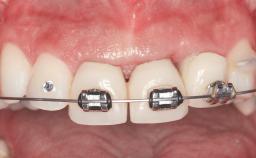

A 45-year-old woman was referred for management of an infection associated with two implant-supported crowns replacing the maxillary central incisors. Two tissue-level implants had been placed and restored with cemented single metal-ceramic crowns in those sites 4 years previously. The patient presented with a draining sinus (i.e. a pathological duct from an abscess cavity to a surface) 3 mm from the midfacial peri-implant mucosal margin of the maxillary right implant crown. She was in good general health, did not smoke, showed a good oral hygiene status, and had no history of periodontal disease. The implants were well positioned. While the patient was very satisfied with the appearance of her crowns, she had noted that the peri-implant soft tissue had receded since their insertion and was concerned about the possibility of further recession.